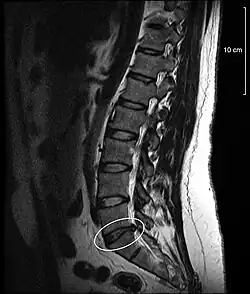

Spinal disc protrusion visible in MRI

[1] A disc protrusion is a medical condition that can occur in some vertebrates, including humans, in which the outermost layers of the anulus fibrosus of the intervertebral discs of the spine are intact but bulge when one or more of the discs are under pressure.

A disc protrusion may progress to a spinal disc herniation, a condition in which there is a tear in the anulus fibrosus.[2] The most common area to have a disc protrusion is in the Lumbar Spine, specifically L-5.[2]